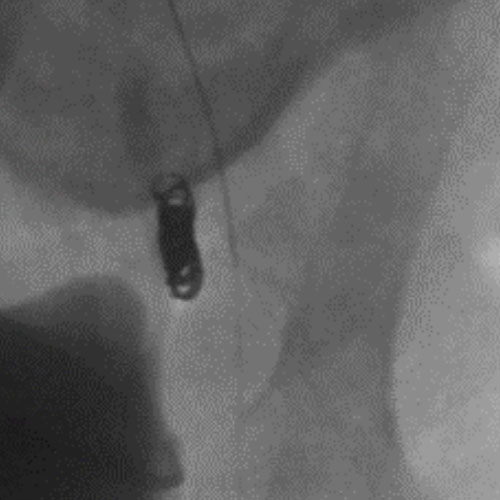

3 vs 2 Coils

Ruby Standard Coil shown  in right subclavian medial Ruby Standard Coil shown in right subclavian medial

Right Subclavian

Medial

3 Ruby Standard 6x20

Embold Fibered Coil shown  in left subclavian medial Embold Fibered Coil shown in left subclavian medial

Left Subclavian

2 Embold Fibered Coil 6x20